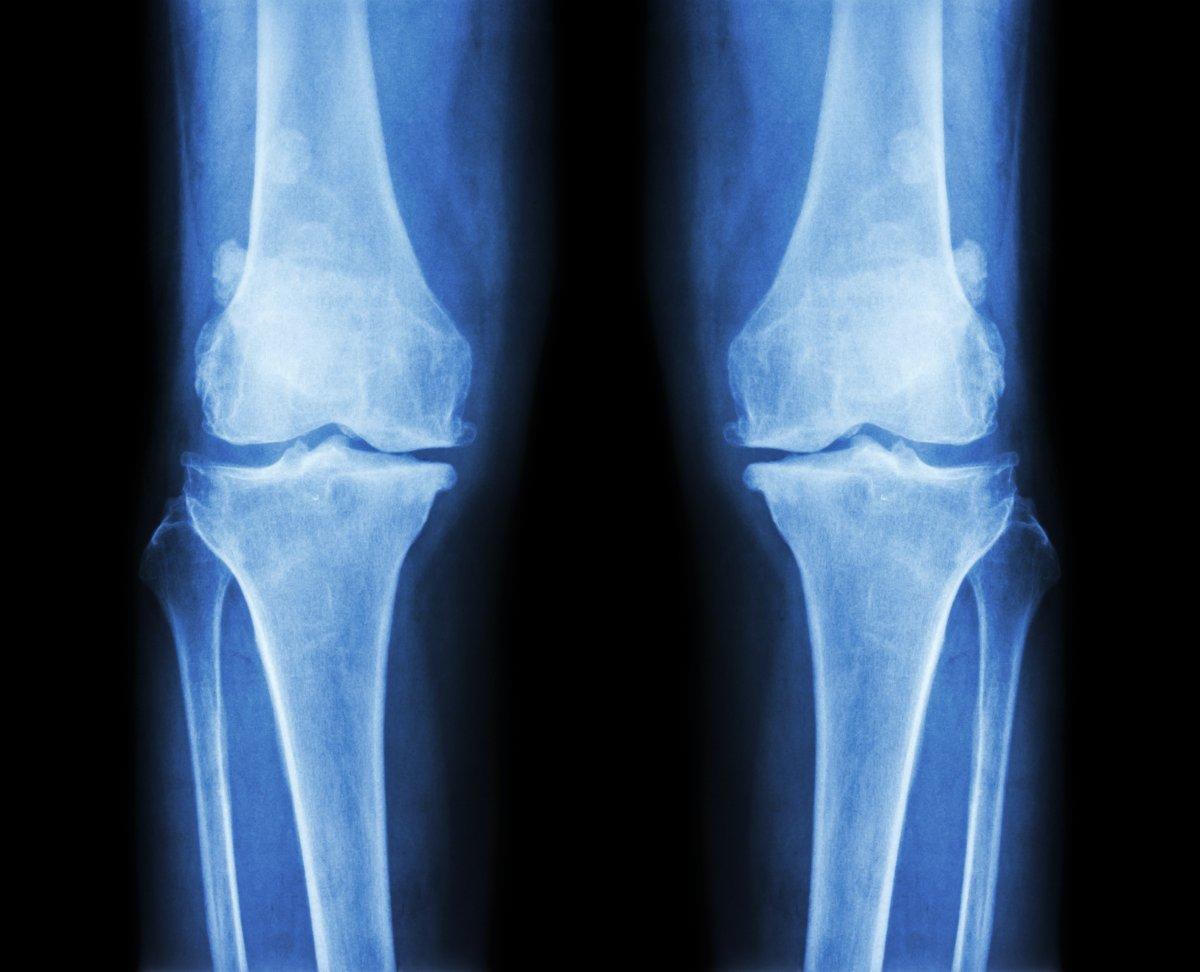

Eklem kireçlenmeleri de bu sorunlar arasında ilk sıralarda yer alıyor.

Yaş almanın yanı sıra aşırı kilo, hareketsizlik ve bilinçsiz spora bağlı olarak gelişen eklem kireçlenmeleri, her yaştan insanın yaşam konforunu elinden alabiliyor.

Her türlü sağlık sorununda olduğu gibi eklem kireçlenmelerinde de erken tanının önemine dikkat çeken uzmanlar, şiddetli ağrılar, eklemlerden ses gelmesi, eklemlerde tıkırtı hissi, günlük aktivite sırasında takılma ya da kilitlenme gibi sorunlar yaşandığında bir uzmana başvurulması gerektiği konusunda uyarıyor.

3 günden fazla süren ağrılar için endişelenilmesi gerektiğini DHA’ya anlatan Kızılay Kağıthane Hastanesi doktorlarından Ortopedi ve Travmatoloji Uzmanı Op. Dr. Hakkı Yıldırım, “Bu ağrılar da aylarca süren ve giderek şiddetini artıran dayanılmaz ağrıların öncüsü olabilir. Yaş almaya bağlı olarak oluşan eklem kireçlenmeleri aniden ortaya çıkabilir, yavaş bir şekilde sinsice ilerleyebilir ya da travmaya bağlı olarak gelişebilir.

Pek çok hastalıkta olduğu gibi eklem kireçlenmelerinde de erken tanının büyük bir önemi bulunuyor. Vücudun eklem bölgelerinde oluşan ağrıların sesine kulak vererek eklem koruyucu cerrahiye başvurmak, yaşam konforunun sürdürülebilirliği açısından oldukça kritik.” dedi.